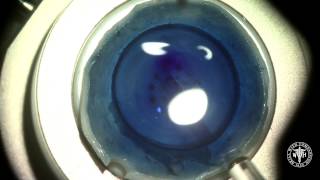

DMEK surgery using a modified Alcon B cartridge video

DMEK surgery using a modified Alcon B cartridge

DMEK surgery using a modified Alcon B cartridge